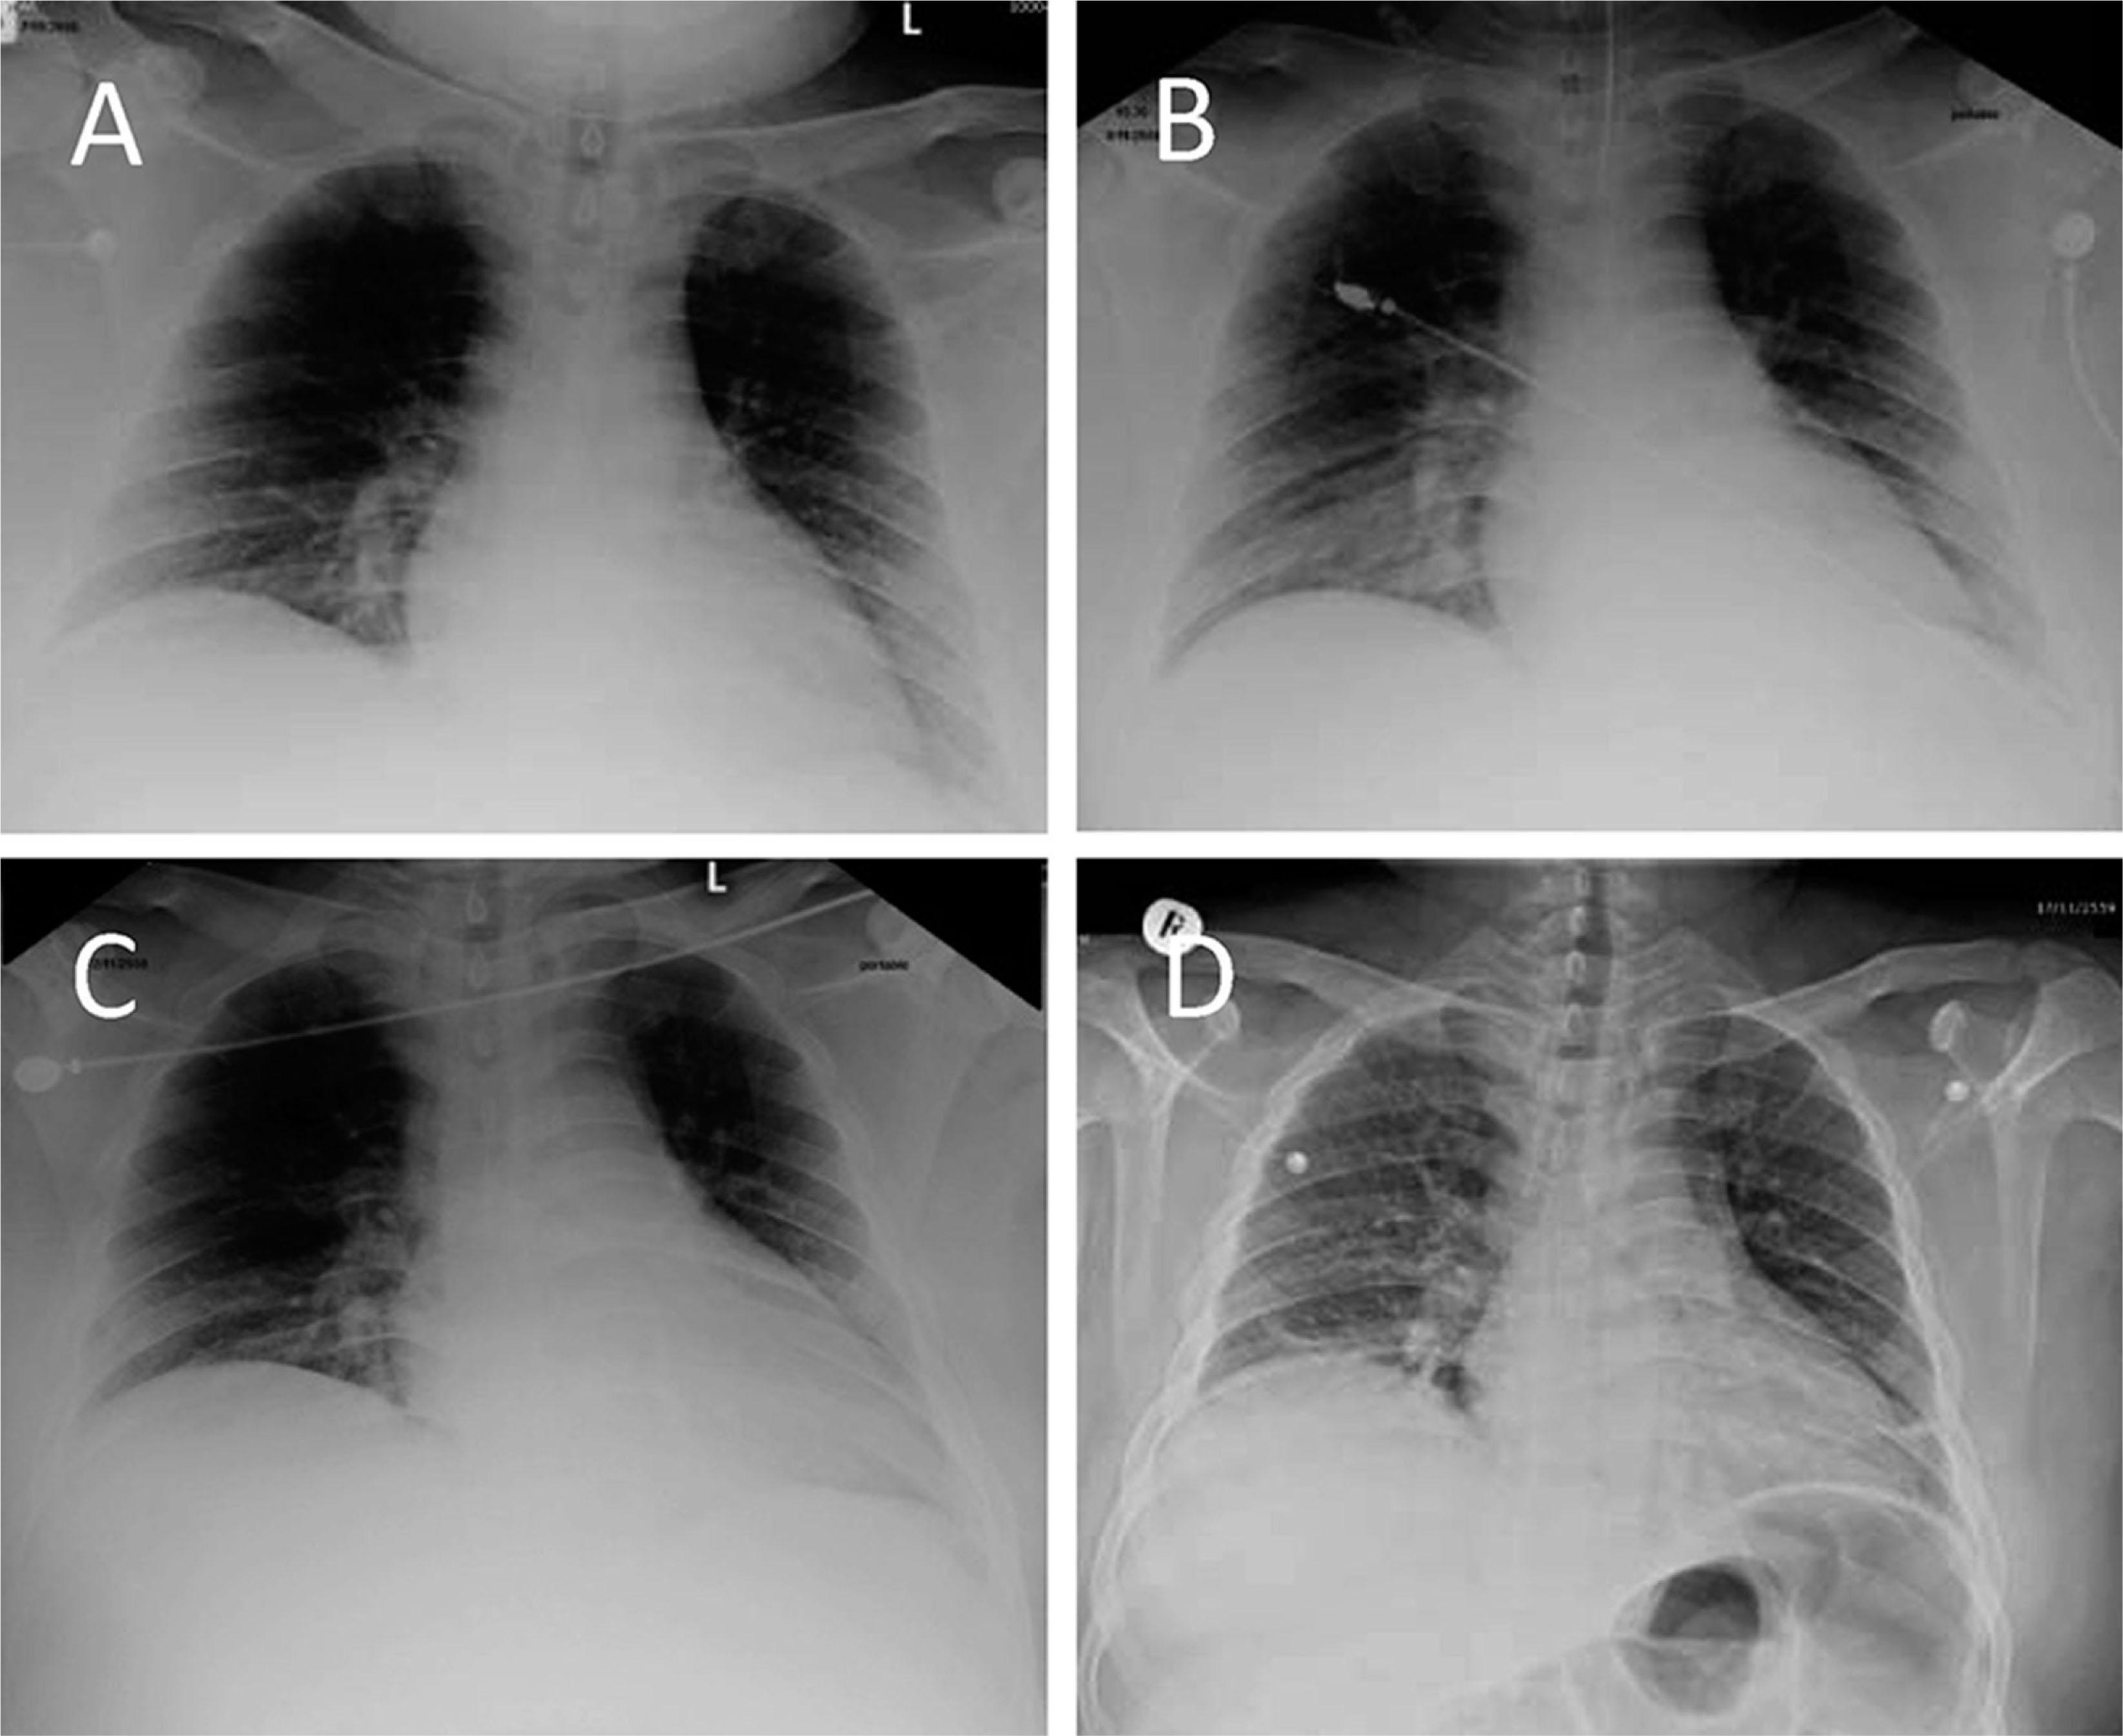

A. Posterior–anterior chest X-ray image demonstrating a slight radiographic sign that suggests interstitial pulmonary edema. B. Supine radiogram demonstrating redistribution of lung circulation from base to middle, suggestive of pulmonary congestion. C. Endotracheal tube inserted after persistent pulmonary congestion. D. Posterior–anterior chest X-ray image showing with normal lung marking and heart size.

A 27-year-old man presented with a 3-day history of high-grade fever, nausea, vomiting, and arthralgia. He denied any relevant past medical history or underlying disease. Physical examination revealed obesity (calculated body mass index (BMI) = 39.6 kg/m2), body temperature of 39.0 °C, blood pressure of 120/95 mmHg, and a respiratory rate of 22/min. Examination of his cardiovascular, respiratory, and central nervous systems found they were within normal range. His liver span was 10 cm without splenomegaly. He had a slight tenderness to percussion over his entire abdomen. His arms were noted for ecchymosis. On the day of his admission to our hospital, laboratory test results revealed a hemoglobin level of 15.8 g/dL, white blood cell count of 3,500 cells/mm3, platelet count of 15,000 cells/mm3, total bilirubin at 2.3 mg/dL, direct bilirubin at 1.9 mg/dL, aspartate aminotransferase (AST) of 7,425 U/L, alanine aminotransferase (ALT) of 2,125 U/L, total protein of 5.9 g/dL, albumin of 3.4 g/dL, and an estimated glomerular filtration rate (eGFR) of 84.07 mL/min/1.73 m2. The dengue nonstructural protein 1 (NS1) antigen test was positive. Chest radiography showed that his lungs were clear with no infiltrates. He was diagnosed with severe dengue infection; initial treatment included an intravenous infusion with 5% dextrose in normal saline solution for 48 h. On day 3 in hospital, he developed hemoptysis and progressive dyspnea. His hemoglobin level at this time was 10.9 g/dL with a platelet count of 13,000 cells/mm3, prothrombin time (PT) of 14.7 s (reference range: 10.5–13.5 s; international normalized ratio: 1.26), partial prothrombin time (PTT) of 39.6 s (reference range: 22.0–33.0 s), thrombin time (TT) of 32 s (reference range: 14.0–21.0 s), and fibrinogen at 286 mg/dL (reference range: 178.1–394.6 mg/dL). Respiratory support with mechanical ventilation was initiated to treat respiratory failure. He received 8 units of leukocyte-poor packed red cells, 5 units of leukocyte-poor platelet concentrate, 1 unit of single donor platelets, 3 units of fresh frozen plasma, and 10 units of cryoprecipitate in an effort to counteract the hemoptysis. However, hemoptysis did not respond to the aforementioned blood component therapy, and the estimated blood loss was 1,500 mL. A chest radiograph taken at this time was notable for showing pulmonary congestion (Figure 1A, B), while his hemoglobin level decreased to 9.5 g/dL. In an effort to counteract the hemoptysis, when rFVIIa (100 μg/kg) was administered intravenously, hemoptysis ceased within 30 min. However, the patient developed hemoptysis again during routine suctioning from the endotracheal tube; he was treated with second and third doses of rFVIIa (100 μg/kg; intravenously). His respiratory condition improved 3 days later (Figure 1C, D). Klebsiella pneumoniae was identified in sputum culture, for which he was treated with intravenous carbapenem (500 mg every 8 h for 14 days). During his second week in hospital, the laboratory test results included a hemoglobin level of 8.7 g/dL, white blood cell count of 5,200 cells/mm3, and platelet count of 117,000 cells/mm3 with evidence of bleeding. His blood smear was consistent with a diagnosis of hemolysis (Figure 2); a direct Coombs test gave a positive result, but an indirect Coombs test gave a negative result. Other laboratory test results were notable for high levels of lactate dehydrogenase (LDH of 677 U/L; reference range: 240–480 U/L). Serum was slightly positive for antinuclear antibodies (ANA), but anti-dsDNA, anti-nRNP, and anti-Sm antibody tests gave negative results, as did a test for Mycoplasma pneumoniae. The patient was diagnosed as having severe dengue infection associated with AIHA. His blood was sent for antibody screening following the guidelines of the British Committee for Standards in Haematology (BCSH): the screening results revealed only nonspecific antibodies. He was treated with an oral form of ferrous sulfate and folic acid and his hemoglobin level returned to normal in 2 months after discharge (Table 1).